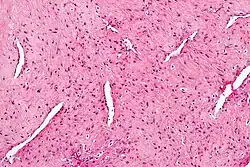

Histologisches Bild eines juvenilen Nasenrachenfibroms. H-E-Färbung, hohe Vergrößerung.

Das histologische Bild wird von dünnwandigen Gefäßen ohne Myozyten und Bindegewebszellen geprägt. Zur Molekularbiologie gibt es noch wenig Daten. Es wurde eine erhöhte Expression von c-myc, VEGF, bFGF, PDGF, c-kit, H-Ras und TP53 beobachtet. Auch β-Catenin war überexprimiert.[3] Es bestehen Hinweise, dass das biologische Verhalten durch molekularbiologische Eigenschaften beeinflusst wird. Eine erhöhte Expression von VEGF war mit einer Invasion der Schädelbasis und vermehrter Blutungsneigung assoziiert. Die Befunde müssen jedoch noch an größeren Kollektiven bestätigt werden.[4]